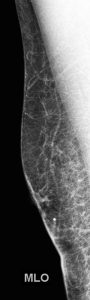

A bilateral diagnostic mammogram was performed. Images of the right breast shown here do not demonstrate any mammographic abnormality under the BB skin marker: